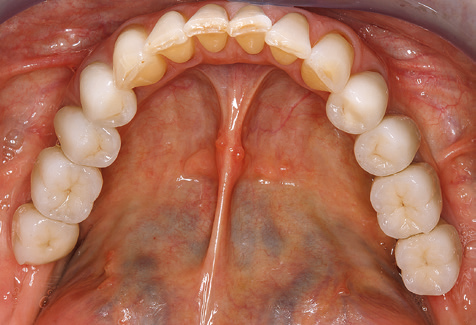

Eine 52-jährige Patientin stellte sich nach Zahnverlust im 3. Quadranten erstmals 2004 vor. Sie hatte den Wunsch nach einer prothetischen Neuversorgung. Im Rahmen der parodontologischen und radiologischen Diagnostik zeigte sich ein ausgeprägter parodontologischer Behandlungsbedarf. Die Zähne 48, 28, 27 zeigten zudem eine infauste Prognose und wurden entfernt (Abb. 1). Nach der erfolgreich abgeschlossenen systematischen PARTherapie wurde eine festsitzende implantatprothetische Versorgung mit Insertion von fünf Implantaten in Regio 35, 36, 37 und 46, 47 durchgeführt. Die prothetische Versorgung der natürlichen Zähne erfolgte mit verblendeten Zirkonoxidkeramikkronen, die Implantate wurden mit zweiteiligen individuellen Zirkonoxidabutments und ebenfalls verblendeten Kronen aus einer Zirkonoxidkeramik versorgt (Cercon base colored, Dentsply Sirona Lab). Die definitive Insertion der prothetischen Versorgung erfolgte im Jahr 2005.

Aufgrund der bestehenden parodontalen Vorerkrankung erfolgte die unterstützende Parodontaltherapie (UPT) in den ersten Jahren in einem DreiMonatsIntervall. Dabei zeigte die Patientin eine hohe Motivation und gute Compliance. Bei den jährlich erhobenen Sondierungsbefunden zeigten sich stabile parodontale Verhältnisse mit einem BOPIndex unter fünf Prozent. Aufgrund der stabilen parodontalen Situation und der guten Mitarbeit der Patientin wurde ab dem sechsten Jahr der prothetischen Funktionsphase das Recallintervall auf halbjährlich umgestellt. Auch mit diesem veränderten Recallintervall zeigten sich bei der jeweils jährlichen Aufnahme des Parodontalstatus stabile parodontale Verhältnisse, ohne Zunahme der Sondierungstiefen und einem BOPIndex unter fünf Prozent (Abb. 2a und b).

Für den klinischen Langzeiterfolg des parodontal kompromittierten Patienten ist die standardisierte und regelmäßige risikoadaptierte Betreuung im Rahmen der UPT der zentrale Baustein des Behandlungserfolgs. Dies gilt in besonderer Weise für Patienten, die nach erfolgreich abgeschlossener parodontaler Sanierung mit Implantaten versorgt wurden (Abb. 11a und b).